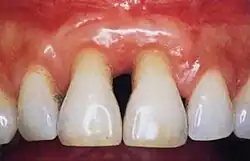

Gingivae

Normal gingiva may range in color from light coral pink to heavily pigmented. The soft tissues and connective fibres that cover and protect the underlying cementum, periodontal ligament and alveolar bone are known as the gingivae. The gingivae are categorized into three anatomical groups: the free, attached and the interdental gingiva. Each of the gingival groups are considered biologically different; however, they are all specifically designed to help protect against mechanical and bacterial destruction.[3]

The junctional epithelium is a collar-like band that lies at the base of the gingival sulcus and surrounds the tooth; it demarcates the areas of separation between the free and attached gingiva. The junctional epithelium provides a specialized protective barrier to microorganisms residing around the gingival sulcus.[4] Collagen fibres bind the attached gingiva tightly to the underlying periodontium including the cementum and alveolar bone and vary in length and width,[4] depending on the location in the oral cavity and on the individual.[5][6] The attached gingiva lies between the free gingival line or groove and the mucogingival junction. The attached gingiva dissipates functional and masticatory stresses placed on the gingival tissues during common activities such as mastication, tooth brushing and speaking.[7]: 80–81 In health it is typically pale pink or coral pink in colour and may present with surface stippling or racial pigmentation.[7]

Healthy gingiva can be described as stippled, pale or coral pink in Caucasian people, with various degrees of pigmentation in other races.[15] The gingival margin is located at the cemento-enamel junction without the presence of pathology. The gingival pocket between the tooth and the gingival should be no deeper than 1–3mm to be considered healthy. There is also the absence of bleeding on gentle probing.[11]